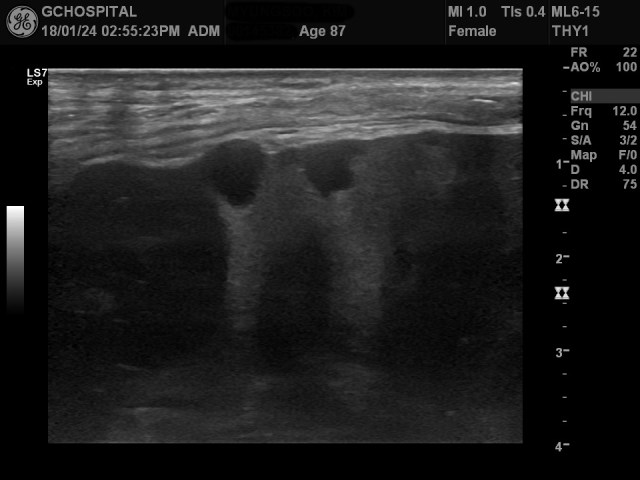

환자는 흉벽에 꽤 심한 통증을 호소하고 있었기 때문에 누워있는 자세에서만 신장을 확인했기 때문에 이런 병변을 놓쳤을지도 모른다는 판단을 했고, 이번에는 아프더라도 참으라고 당부한 다음 Rt. decubitus position에서 다시 복부초음파에 사용하는 curvilinear probe를 사용해서 앞서의 종괴와 8미리 크기의 단순낭종이 있던 부위를 스캔한 게 위 영상입니다(마커에서는 누워있는 상태로 표시됬지만, decubitus position에서 스캔한 영상입니다).

앞서 봤던 8미리크기의 단순낭종은 희미하게 보이지만, 앞서 보였던 2.5센티미터 크기의 고형성 종괴는 여전히 뚜렷하게 확인이 되지 않고 있습니다.